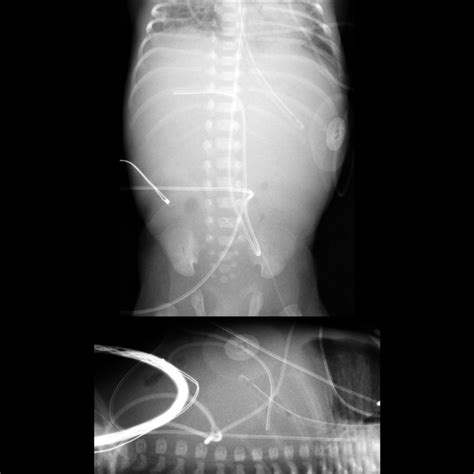

• Malposition: Incorrect placement of the catheter can lead to ineffective therapy or complications such as arrhythmias.

To mitigate these risks, healthcare providers must adhere to strict protocols for insertion, maintenance, and monitoring of the Umbilical Venous Catheter. Regular assessment of the catheter site, prompt removal if signs of infection are detected, and careful monitoring of the infant's vital signs are essential.